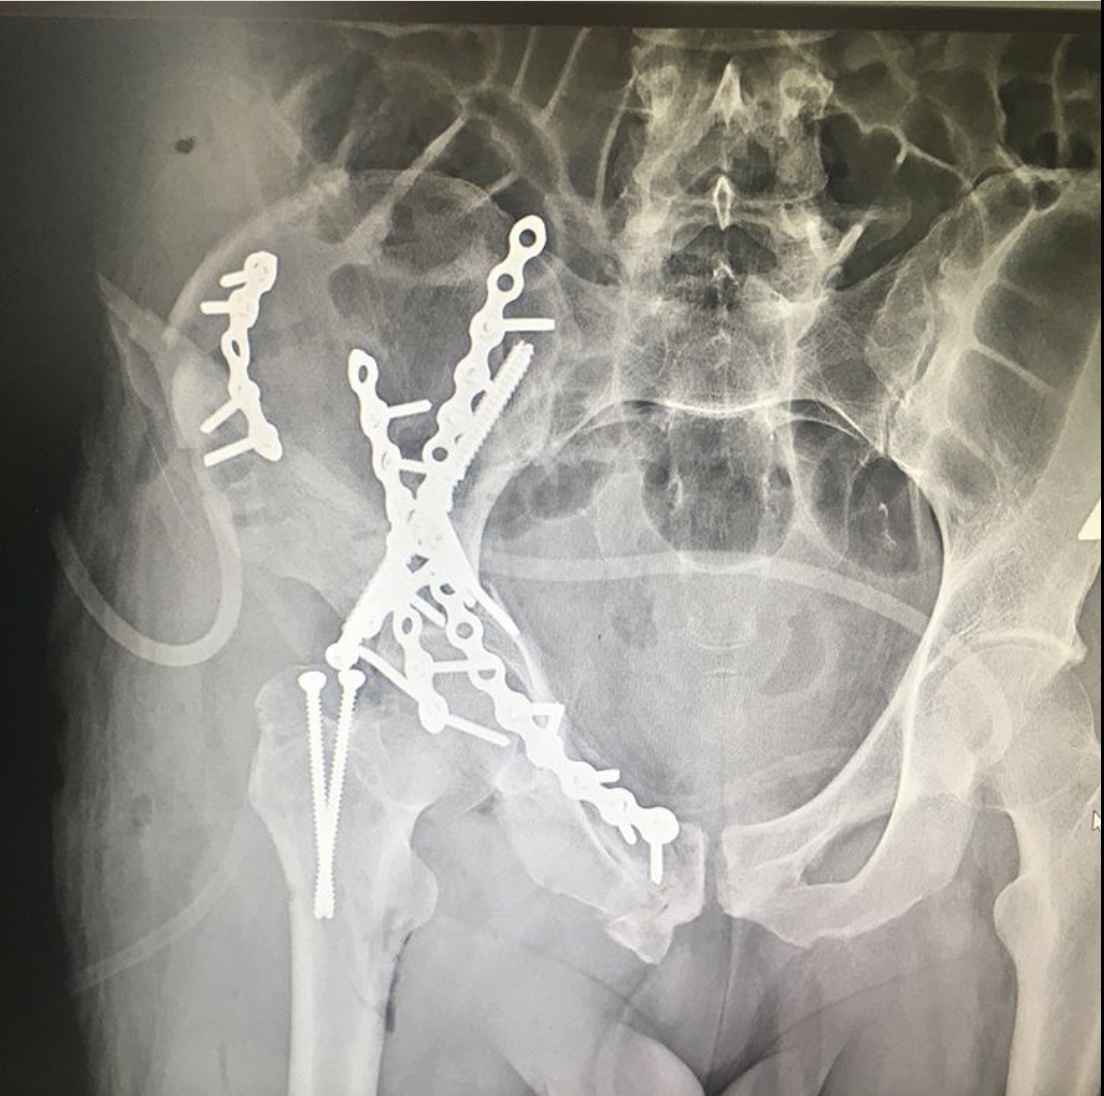

Травматологи ГКБ 7 Казани выполнили сложную операцию при травме вертлужной впадины

Ещё один случай тяжелой травмы вертлужной впадины с разнонаправленным смещением отломков.

Как рассказал хирург – травматолог – ортопед ГКБ 7 Казани Руслан Ильгизарович Закиров, после стабилизации гемодинамических показателей был выполнен остеосинтез реконструктивными пластинами и винтами. При такой травме вероятность «выживания» тазобедренного сустава очень невелика. Но при любом развитии ситуации созданы условия для дальнейшего лечения и реабилитации пациента.